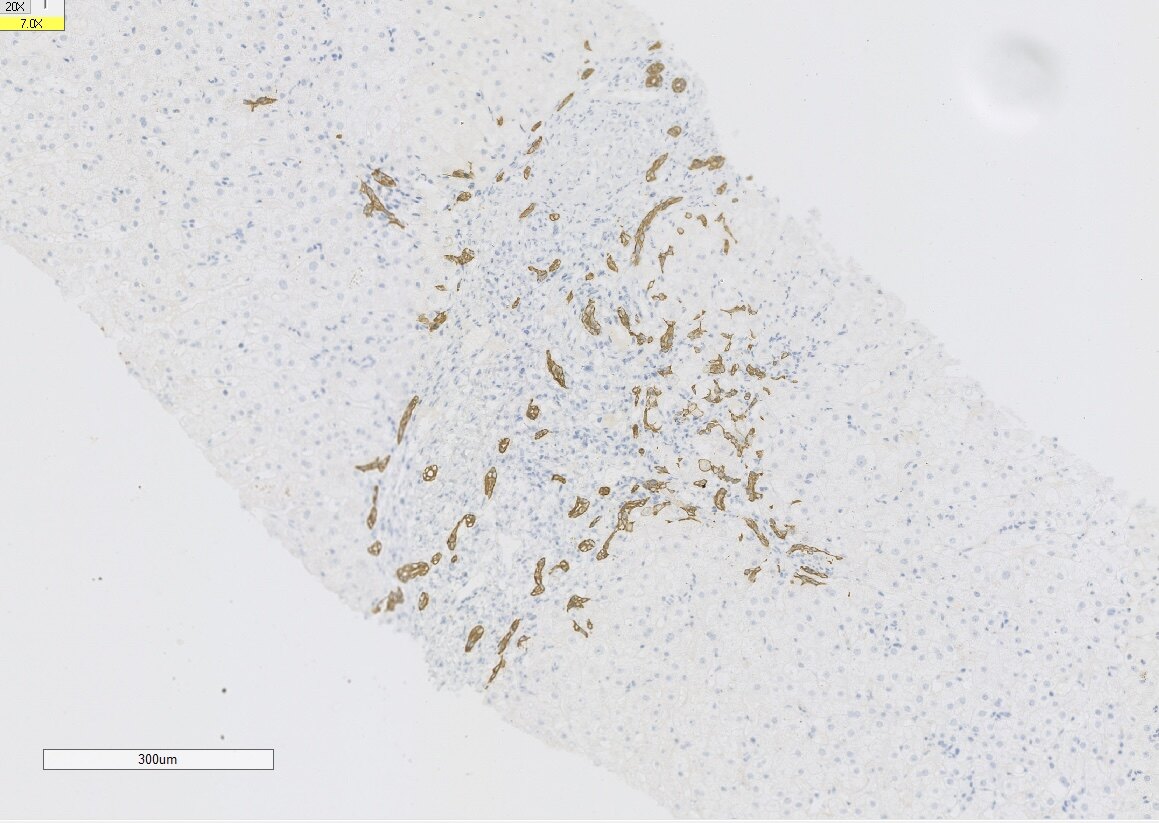

肝活检的意义

经常碰到长期肝功能异常的患者,常规检查做了仍不能找到原因。这时候我会建议进行肝活检,虽然有时候肝活检仍然不能给予一个确切的诊断,但是起码能够知道病变的部位在哪?是肝细胞损伤为主,胆管损伤为主,还是两者兼有,这样我们就能根据不同的患者给予不同的治疗方案,做到精准治疗和个体化治疗!